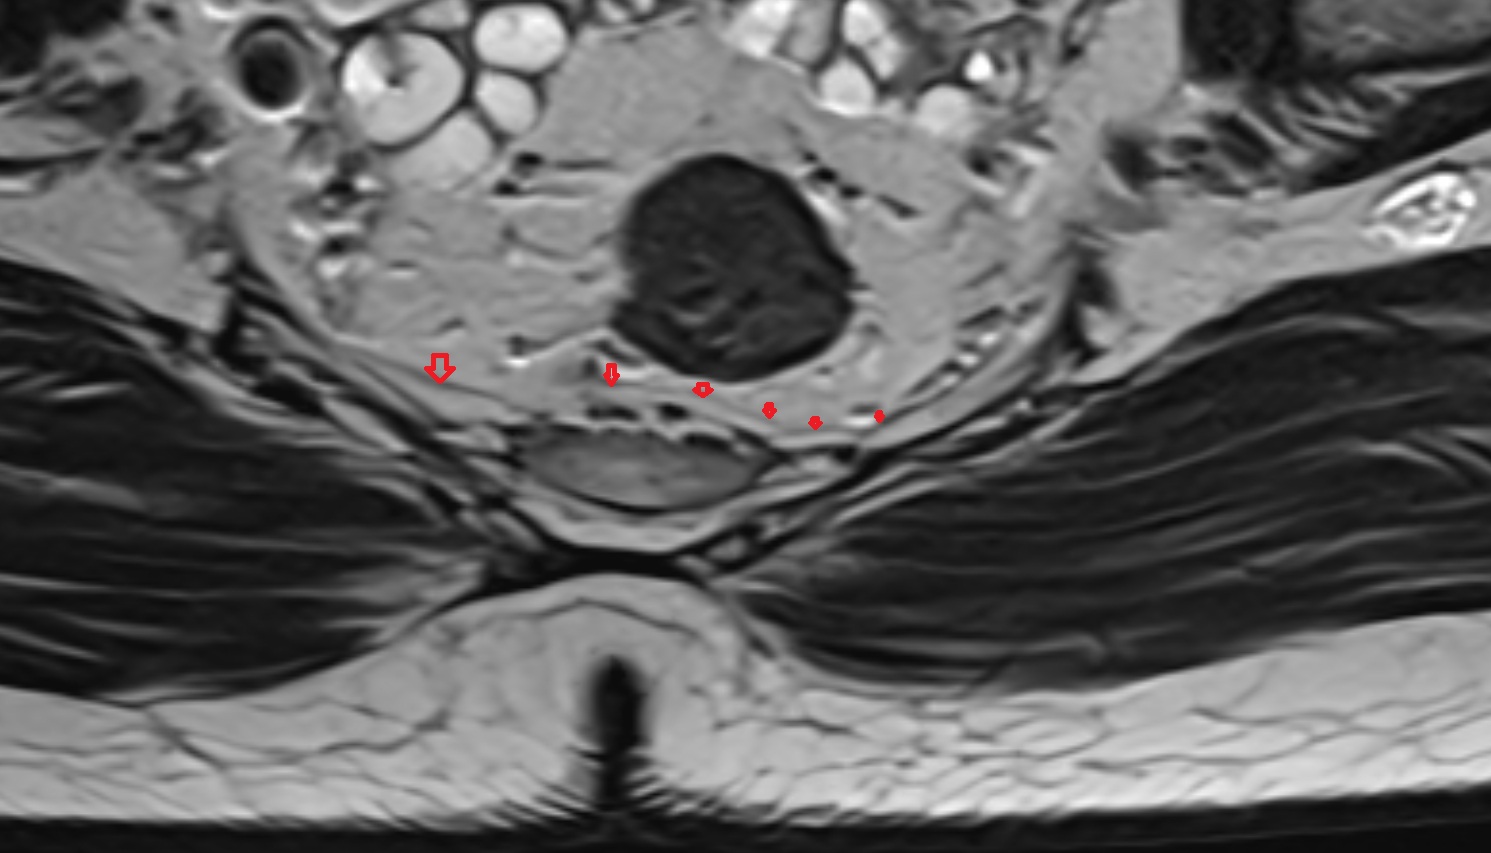

- Rectum

- Mesorectal fascia

- Mesorectum

- Peripheral zone of prostate

- Central zone of prostate

- Transitional zone of prostate